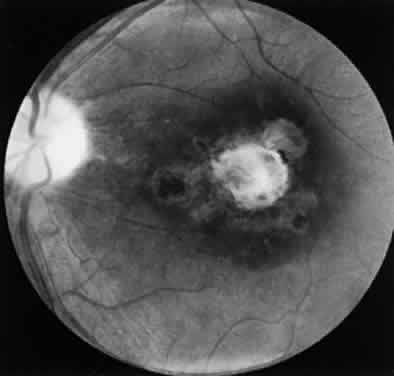

Ocular toxoplasmosis most commonly presents as a focus of necrotizing retinitis (Fig. 7) involving the inner layers of the retina and associated with a whitish fluffy lesion surrounded by retinal edema.6,59 Cells are seen in the vitreous overlying the lesion. The focus of retinitis may be large (Fig. 8) or small (Fig. 9). The retina is the primary site for the multiplying parasites, whereas the choroid and sclera may be the sites of contiguous inflammation. When the choroid is involved by the inflammatory reaction, the lesion is referred to as retinochoroiditis. The organisms are rarely seen in the choroid. The retinal lesion may be small and single or large and multiple and may reach several disc diameters in size. Large granulomas in the posterior segment of the eye frequently are seen in patients with ocular toxoplasmosis (Fig. 10). This is associated with extensive and marked vitreous reaction that precludes visualization of the retina, and the granuloma appears as a yellowish mass surrounded by a red reflex. Punctate outer retinal involvement may be seen in some patients with toxoplasmosis.60 These appear as multifocal, gray-white lesions in the deep retina and at the level of the retinal pigment epithelium accompanied by no overlying vitreous reactions. The lesions may resolve to form fine, granular white dots. This is the earliest finding seen in the rabbit models of ocular toxoplasmosis after the injection of Toxoplasma organisms in the suprachoroidal space. The lesions in the animal model may start as deep outer retinal punctate lesions that later involve the inner layers of the retina and cause the typical focus of retinochoroiditis. Involvement of the macular area is common in patients with congenital toxoplasmosis, and exudative retinal detachment may occur in severe cases. Clumps of inflammatory cells may be seen in the vitreous or over the detached posterior vitreous face. The focus of retinitis may be a manifestation of congenital toxoplasmosis or may be associated with or follow an episode of acquired systemic toxoplasmosis. Patients presenting with recurrent toxoplasmic retinochoroiditis usually are in the second or third decade, but the disorder may occur at any age. Healing of the retinitis is associated with a decrease in retinal edema and flattening of the lesion with evidence of scar formation surrounded by variable amounts of pigment (Fig. 11). The lesion may appear as a punchedout scar with underlying sclera resulting from extensive retinal and choroidal necrosis surrounded by pigment proliferation (Fig. 12), it may become a conglomerate or proliferated retinal pigment cells (Fig. 13), or it may be small and appear as a pigment clump in the retina. The retinochoroiditic scar may harbor the Toxoplasma cysts. Healing also is associated with decrease in the vitreous cells and improvement in visual acuity. Immunologic suppression is associated with recurrence of retinochoroiditis (Fig. 14). Recurrent toxoplasmic retinitis frequently appears as “satellites” or occurs adjacent to a previous scar. Old, inactive lesions often appear to be a conglomeration of previous multiple inflammatory foci (see Fig. 13).

Fig. 8. Severe Toxoplasma retinochoroiditis with large granuloma and overlying vitreous cells. A healed retinochoroiditic scar is seen in close proximity to the granuloma.